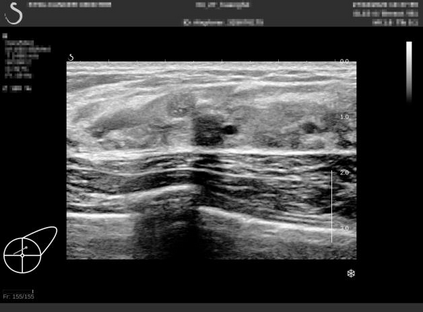

Ultrasonography is an important routine examination for breast cancer diagnosis, due to its non-invasive, radiation-free and low-cost properties. However, it is still not the first-line screening test for breast cancer due to its inherent limitations. It would be a tremendous success if we can precisely diagnose breast cancer by breast ultrasound images (BUS). Many learning-based computer-aided diagnostic methods have been proposed to achieve breast cancer diagnosis/lesion classification. However, most of them require a pre-define ROI and then classify the lesion inside the ROI. Conventional classification backbones, such as VGG16 and ResNet50, can achieve promising classification results with no ROI requirement. But these models lack interpretability, thus restricting their use in clinical practice. In this study, we propose a novel ROI-free model for breast cancer diagnosis in ultrasound images with interpretable feature representations. We leverage the anatomical prior knowledge that malignant and benign tumors have different spatial relationships between different tissue layers, and propose a HoVer-Transformer to formulate this prior knowledge. The proposed HoVer-Trans block extracts the inter- and intra-layer spatial information horizontally and vertically. We conduct and release an open dataset GDPH&GYFYY for breast cancer diagnosis in BUS. The proposed model is evaluated in three datasets by comparing with four CNN-based models and two vision transformer models via a five-fold cross validation. It achieves state-of-the-art classification performance with the best model interpretability.